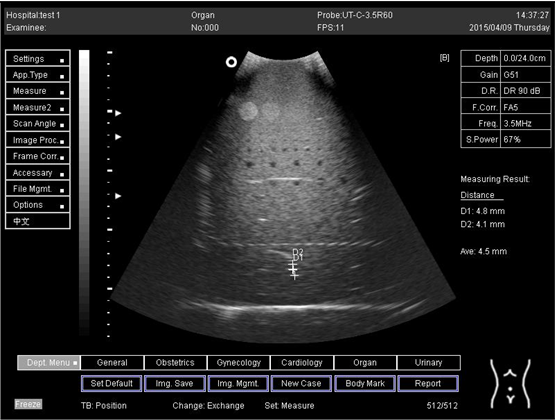

24.0Axial resolution

Biomimetics 07 00130 i021

D1 = 4.8

D2 = 4.1

24.0Lateral resolution